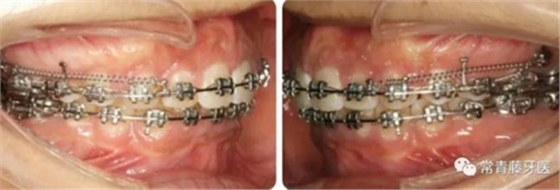

A67、B67之間植入微種植釘整體內(nèi)收上牙列,下頜配合多用途弓整平牙列改善覆合。

繼續(xù)內(nèi)收上牙列,此時(shí)下頜spee曲線基本整平。